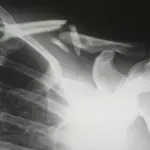

Из иска бийского депутата следует, что о злокачественном образовании в легком у ее супруга они узнали 12 августа 2022 года. Заболевание осложнялось кровохарканьем и легкой дыхательной недостаточностью. В связи с этим его перевели в КГБУЗ "Городская больница №5 Барнаула", где 17 августа Николая Рязанова поместили в стационар отделения торакальной гнойной хирургии.

29 августа ему провели оперативное вмешательство, которое подтвердило факт распространенного новообразования. Операцию проводил заведующий отделением торакальной гнойной хирургии горбольницы №5 Вячеслав Седов. Однако материал для верификации типа опухоли не взяли, что, по мнению Инны Рязановой, является грубым дефектом оказания помощи.

"Он поступил к нам уже с неоперабельным раком, сопровождавшимся кровохарканьем. Мы пытались установить гистологическую принадлежность этого онкозаболевания, но обычными методами это сделать не удавалось. Поэтому решили пойти другим путем. Эти решения не принимаются единолично — только коллективно и с одобрения академика Якова Наумовича Шойхета", — рассказал он.

"На операции мы убедились, что в это прорастание уже вовлечены все сосуды, на этом мы операцию и прекратили. В операционной в это время присутствовал Яков Наумович Шойхет, он посмотрел больного — как говорится, руками в этом убедился. Мы пришли к выводу, что продолжать операцию нельзя, иначе пациент умрет у нас на операционном столе. Если бы в результате диагностики у него началось кровотечение, мы бы уже ничего не сделали", — пояснил медик.